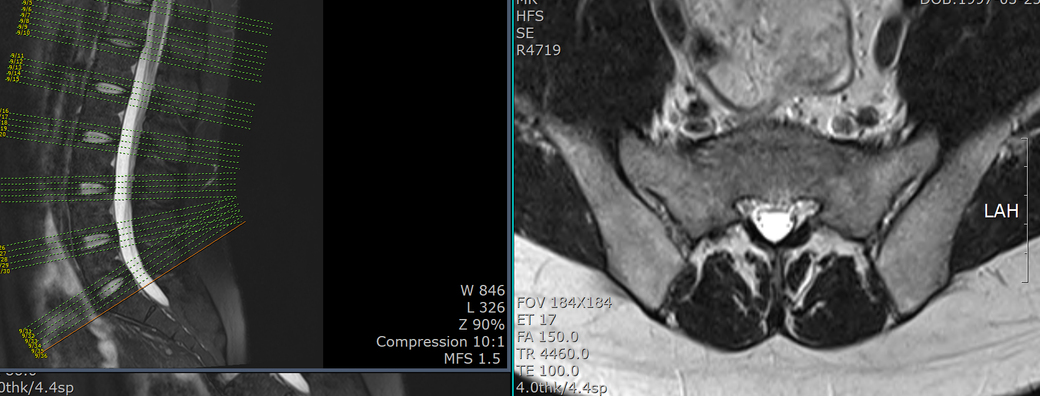

Pulse sequences

- T2WI and T1WI sagittal, T2WI and T1WI axial

- T2WI fat suppression sagittal

- T2WI coronal

- T2WI whole spine sagittal image

- contrast: (-)

< Sagittal whole spine T2WI image >

C4-5, C5-6 disc herniation at sagittal whole spine T2WI image

• 2번 째 사진